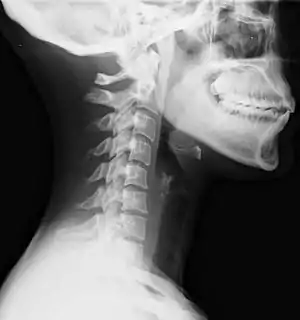

| Lateral view X-ray of whiplash showing a loss of normal lordosis of the cervical vertebrae | |

Diagnosis occurs through a patient history, head and neck examination, X-rays to rule out bone fractures and may involve the use of medical imaging to determine if there are other injuries.[26]